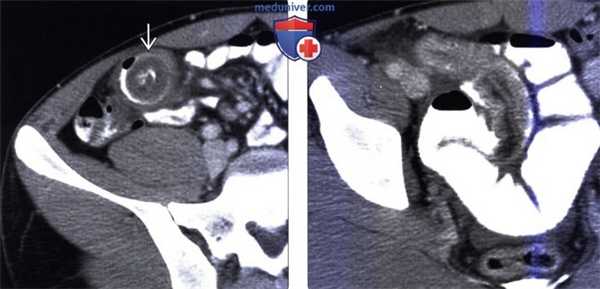

(Слева) На аксиальной КТ с контрастным усилением, выполненной девушке 17 лет, предъявляющей жалобы на боль в животе спастического характера, с наличием болезненности в области нижних отделов правой половины живота, определяется инвагинация дистальных отделов подвздошной кишки.

(Справа) На аксиальной КТ с контрастом у этой же пациентки определяется инвагинация длинного сегмента и дилатация проксимальных отделов тонкой кишки вследствие обструкции. Во время операции было обнаружено, что причиной инвагинации стал инвертированный дивертикул Меккеля.